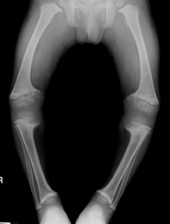

Short stature in infants and children

• The wide range of possible causes must be considered in a child with short stature or abnormal growth. These include normal variants (such as constitutional delay), chronic disease, poor nutrition, endocrine diseases, chromosomal disorders and skeletal dysplasias.